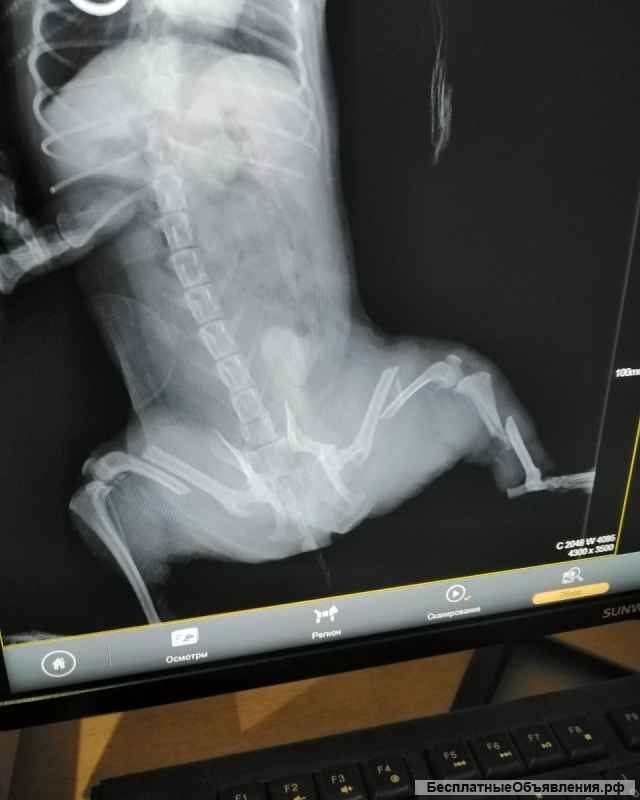

Собачку сбила машина, задние лапы сломаны в трех местах. Хозяева привезли усыплять. Мы забрали его, отвезли в клинику, стоимость операции около 45000 тысяч. Просим помощи, для лечения. Операция на одну лапку прошла вчера, на вторую будет в воскресенье. Операции сложные, на одной лапке загноение пошло... На ней будет 2 месяца стоять аппарат Илизарова. На данный момент внесли предоплату в размере 5000 рублей.